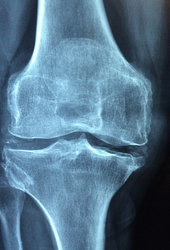

관절염은 관절에 염증이 생기는 질환으로, 통증, 부기, 뻣뻣함, 움직임 제한 등을 유발합니다. 관절염은 여러 가지 원인에 의해 발생할 수 있으며, 치료가 어렵습니다. MSM은 관절염의 증상을 완화하는 데 도움이 될 수 있습니다. MSM은 염증을 감소시키고, 통증을 줄이고, 관절의 유연성을 증가시키는 것으로 연구되었습니다. 예를 들어, 한 연구에서는 관절염 환자들에게 12주 동안 매일 3g의 MSM을 복용하게 하였습니다. 그 결과, 통증과 뻣뻣함이 감소하고, 일상생활에 미치는 영향이 줄어들었다고 보고하였습니다.

연골은 관절의 끝부분에 있는 탄력성 있는 조직으로, 관절의 충격을 흡수하고 마찰을 줄여줍니다. 연골은 나이가 들면서 손상되거나 감소할 수 있으며, 이는 관절의 기능에 영향을 미칩니다. MSM은 연골의 건강을 지원하는 데 도움이 될 수 있습니다. MSM은 연골의 구성 성분인 콜라겐과 글루코사민의 합성을 촉진하고, 연골 분해를 억제하는 효과가 있다고 알려져 있습니다. 예를 들어, 한 연구에서는 관절염 환자들에게 3개월 동안 매일 1.5g 또는 6g의 MSM을 복용하게 하였습니다. 그 결과, MRI 검사에서 연골의 손상 정도가 감소하였다고 보고하였습니다.